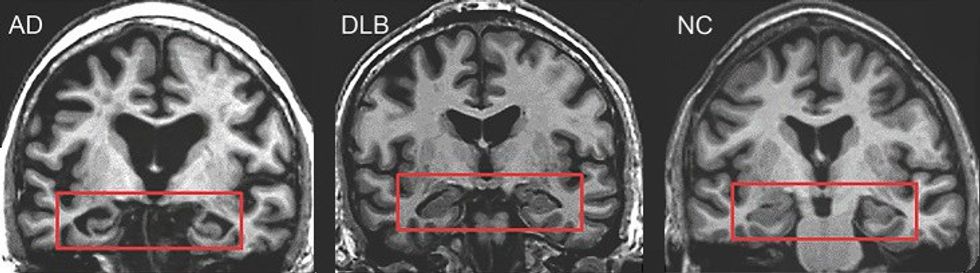

MRI of brain showing hippocampus atrophy (red rectangles), more prominent in Alzheimer's disease

|Wikimedia Commons Licences